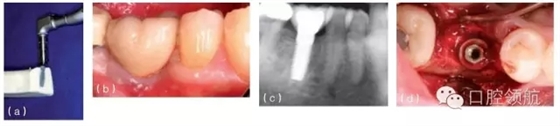

圖10.4 (a)在頜骨模型上,環(huán)鉆置于種植體上。環(huán)鉆是空心柱狀的,鉆的末端有切割螺紋。它放在種植體上,可以順著種植體邊緣周的骨組織的切線方向環(huán)行去除骨組織,從而使種植體移除造成的創(chuàng)傷減到最小。(b)種植單冠的頰面觀,種植修復(fù)后患者產(chǎn)生持續(xù)性的疼痛,且無(wú)法緩解,需要取出種植體。(c)根尖片顯示種植體正常。(d) 取出牙冠,翻瓣暴

露種植體。(e)用環(huán)形鉆取出包繞種植體的骨環(huán)。(f)環(huán)形鉆包繞種植體,環(huán)形切削達(dá)種植體全長(zhǎng)。(g)環(huán)形鉆切削完畢,(環(huán)形鉆中心的)切除的骨組織包繞種植體,種植體周圍已被分離,只有根尖區(qū)還有骨組織與種植體相連接。將使用一種器械,置于骨環(huán)周,切斷根尖區(qū)的骨組織。(h)包含種植體在內(nèi)的骨環(huán)被取出。(i)取出后置于外科盤上,可見(jiàn)種植體及附著周圍薄層的骨組織。種植體植入時(shí)曾植骨,種植體周可見(jiàn)殘留的顆粒狀的骨移植材料。(j)種植體移除后,去骨創(chuàng)面的牙合面觀。(k)將骨移植材料(同種異體骨與異種骨移植材料混合)放置在去骨創(chuàng)面中。(l)放上屏障膜,用釘固定。